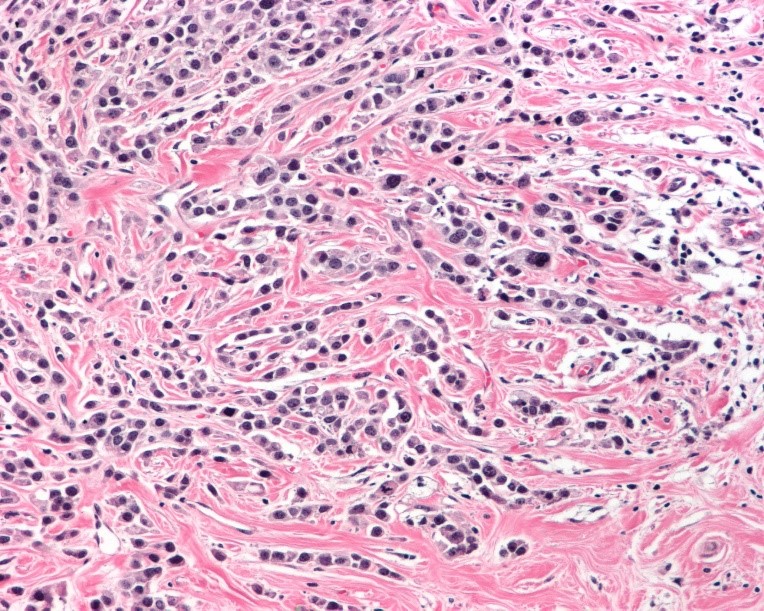

Imágenes microscópicas de la neoplasia en mama:

Carcinoma metaplásico productor de matriz o de tipo mixto, con respuesta categoría I de RCB o Miller y Payne 3.

2) Que clasificación usaría para este caso y a que categoría corresponde?

Hay varias clasificaciones vigentes:

** Organización Mundial de la Salud que clasifica el carcinoma metaplásico en 2 grandes grupos:

a)Tipo epitelial

b)Tipo mixto